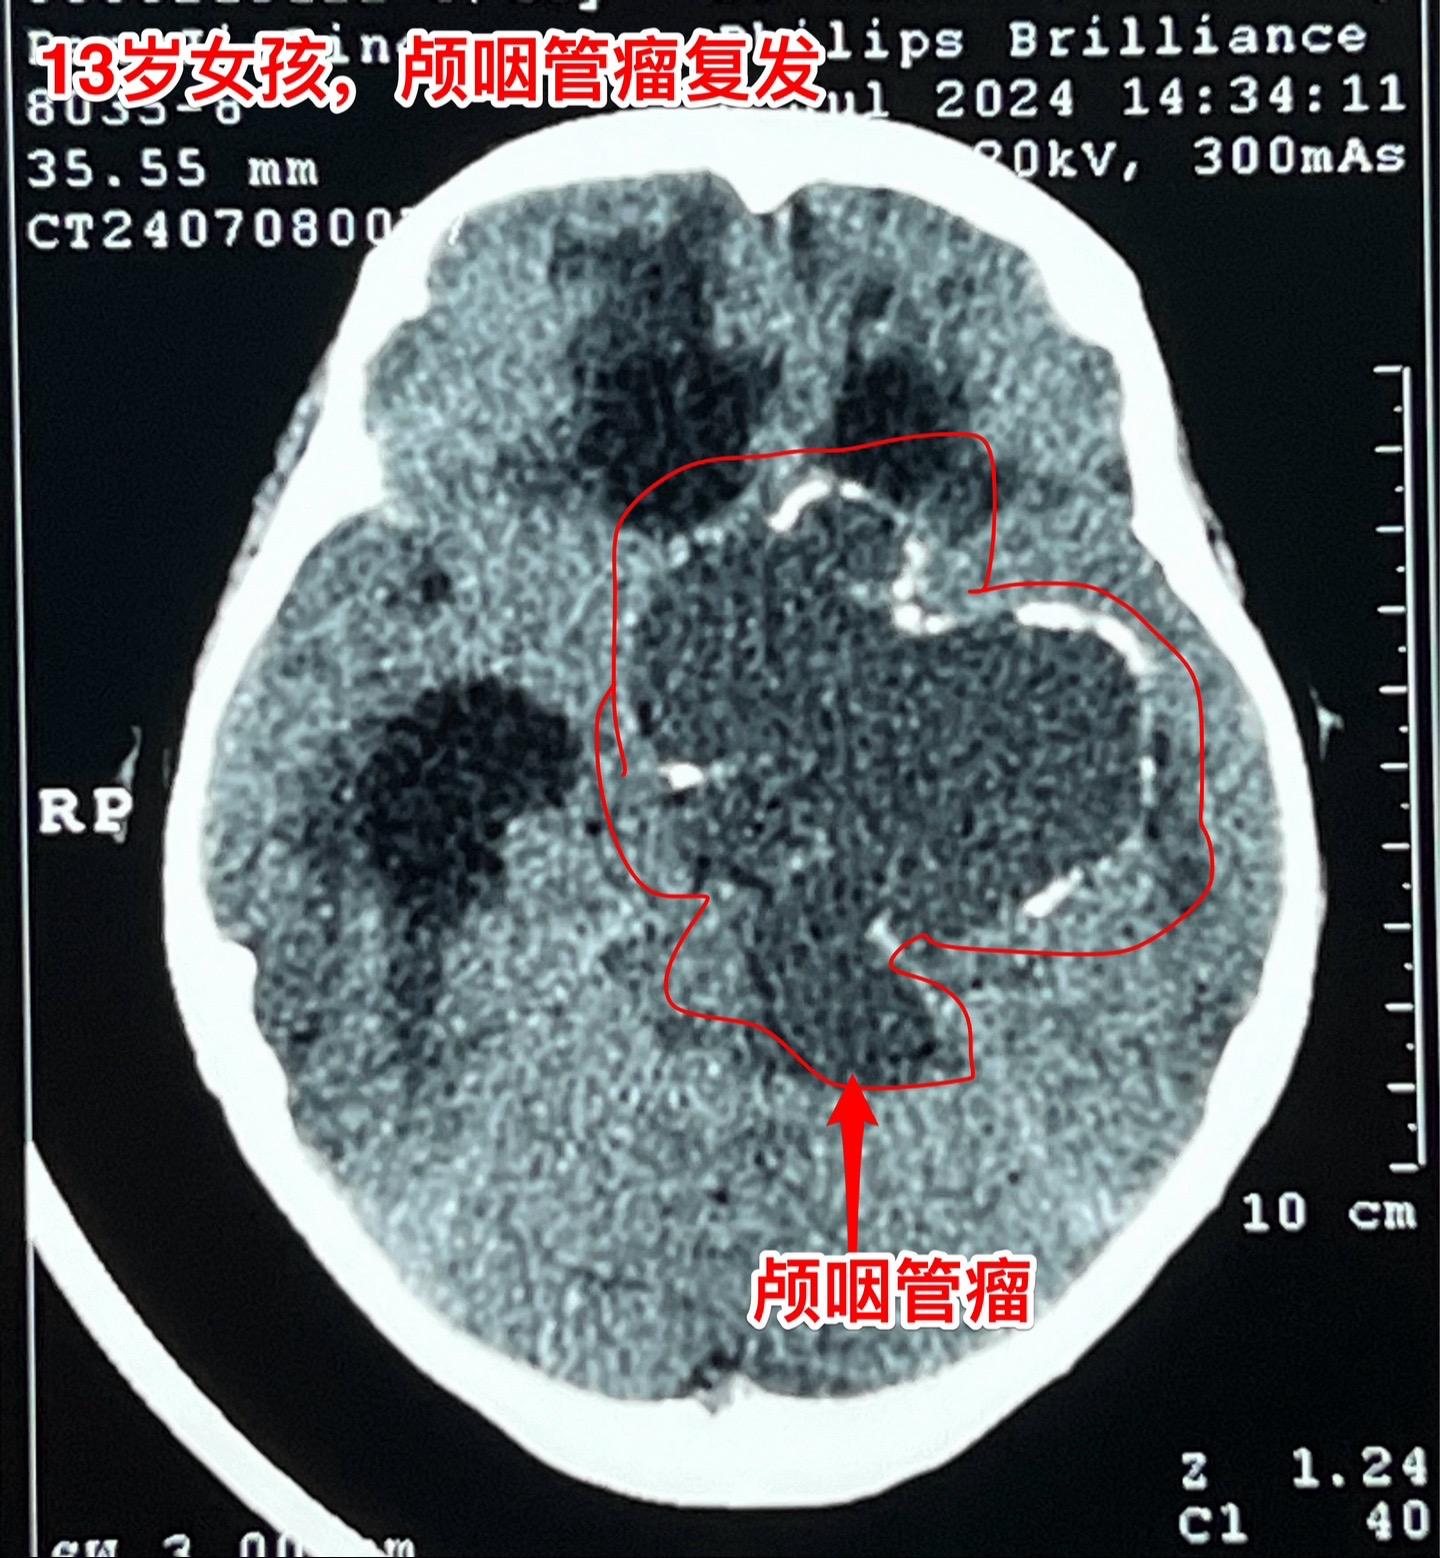

复发的巨大颅咽管瘤,难度很大。13岁四川女孩子,2022年6月在外院行开颅手术切除颅咽管瘤。半年后颅咽管瘤复发,家长采用中药治疗。中药控制颅咽管瘤的效果也不理想,肿瘤还在继续生长。 复发肿瘤体积越来越大,患儿曾经出现过头痛、呕吐、多睡症状。经过补充糖皮质激素后症状有好转。额部骨头逐渐出现隆起,见图4、5。 2024年7月16日作了开颅手术,将颅咽管瘤完全切除。肿瘤体积大,压迫脑干,而且与周围的血管粘连紧密,手术过程很艰难,最终获得完全切除。 手术后患儿很虚弱